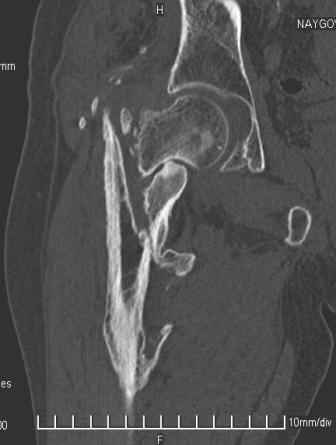

Больной Н. 44 года травма 1,5 года назад июнь 2008 года чрез-под вертельный перелом правого бедра. Во время лечения у больного развился алк. делирий, проводилось консервативное лечение перелома.

Беспокоят боли, укорочение конечности.Укорочение 3 см. Ногу поднимает, сгибание ограничено, ротационные движения в полном объеме.На КТ перелом сросся за счет костной мозоли.Что делать?

Уважаемый Глеб! Укорочение наверное побольше, да и наружно-ротационная установка скорее всего присутствует. Суставная щель прекрасная, головка живее всех живых. Ратую за подвертельную с латерализацией: исключает нарушение механической оси («исключает вальгус в коленe»), максимально удлиняет без натяжения m.iliacus. Для иллюстрации остеотомия-переделка (слава богу не автопеределка) у мужчины 65 лет.